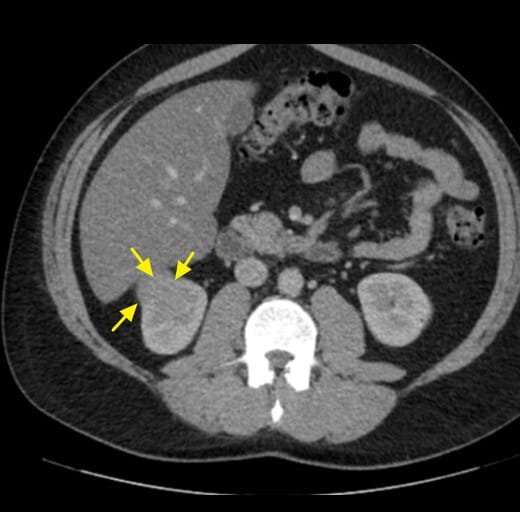

영상소견 정리

CT/ MRI 소견

조영증강 영상에서 고형성 종괴 + 중심 괴사, 혈관 침범

| CT/ MRI 소견 |

| ✅ 조영증강 고형 종괴 |

| CT에서 조영제 주입 시 병변이 비정상적으로 밝게 조영되며, 실질보다 높은 밀도 |

| ✅ 중심 괴사(necrosis) |

| 종양이 자라면서 내부 혈류 공급이 떨어져 중심부 괴사가 흔하게 발견. |

초음파 소견

신세포암(Renal cell carcinoma)은 복부 초음파에서 우연히 발견되는 경우가 많으며, 종괴의 존재 여부와 낭성/고형성 여부를 파악하는 데 유용합니다.

| 🟩 고형 종괴(hyperechoic 또는 isoechoic mass) |

| 주로 신장 실질 내에 존재하는 경계 명확한 고형 병변으로 보이며, 주변 실질에 비해 에코가 높거나 비슷한 양상을 보입니다. |

| 🟩 신장 외부 돌출 또는 변형 |

| 종양이 신장 피막을 넘어서 돌출되거나, 신장의 외형이 비정상적으로 변형된 경우 진행된 병기 가능성을 고려합니다. |